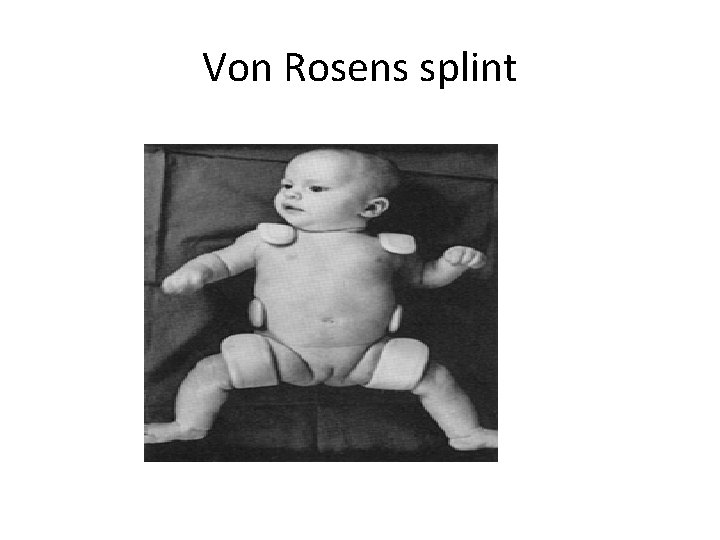

Developmental Dysplasia Of The Hip DDH Definition Dysplasia

Developmental Dysplasia Of The Hip DDH Definition Dysplasia

Developmental Dysplasia Of The Hip DDH Definition Dysplasia

Developmental Dysplasia Of The Hip DDH Definition Dysplasia

Developmental Dysplasia Of The Hip DDH Definition Dysplasia

Developmental Dysplasia Of The Hip DDH Definition Dysplasia

Developmental Dysplasia Of The Hip DDH Definition Dysplasia

Developmental Dysplasia Of The Hip DDH Definition Dysplasia